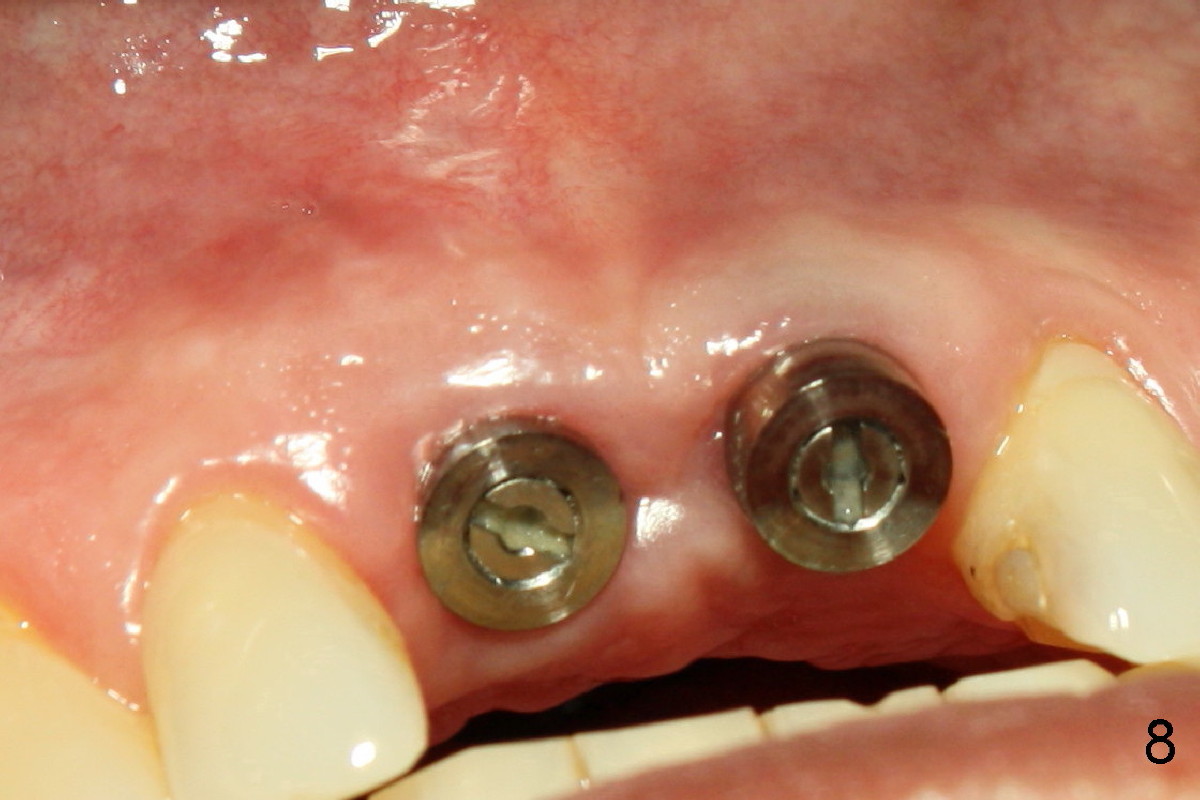

Wounds heal uneventfully. Two months later, an implant is placed at the site of #8 (Fig.5).  Fig.4 is a preop X-ray, showing graft (*).  Two weeks later, swelling and pain recur (Fig.7).  Amoxicillin 500 mg tid is prescribed for a week.  Symptoms and signs improve after antibiotic treatment (Fig.8).  A month later, the patient complains tenderness on touching the implant of #8 without swelling.  A X-ray film is taken (Fig.6).  The symptom is again controlled while taking oral Clindamycin and relapses when treatment is terminated.  What should we do?